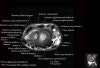

- Axial section

Axial PD fat suppressed evaluates the tendons of the wrist and carpal tunnel, including the median nerve.